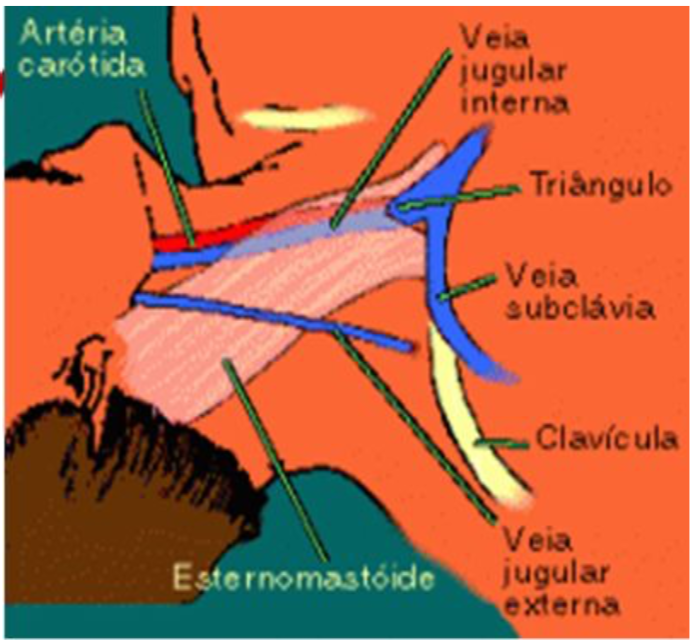

A veia jugular interna situa-se ântero-lateralmente à artéria carótida interna, na sua metade proximal sob o músculo esternocleidomastóideo e sua metade distal no triângulo formado pelas porções clavicular e esternal do músculo esternocleidomastóideo, e pela clavícula. Une-se com a veia subclávia sob o terço proximal da clavícula.

A VJI tem trajeto relativamente constante, porém pode sofrer variações anatômicas. deve ser dado preferência a punção da jugular direita pelo menor risco de lesão da cúpula pleural e impossibilidade de lesão do ducto torácico.

Existem três vias de acesso de veia jugula podem ser utilizadas para a cateterização da veia jugular interna: a anterior, a lateral e a posterior.

- Escolher local de punção: cruzamento da jugular externa com o esternocleidomastoideo ou 5 cm acima da clavícula no bordo posterior do esternocleidomastoideo. Palpar carótida